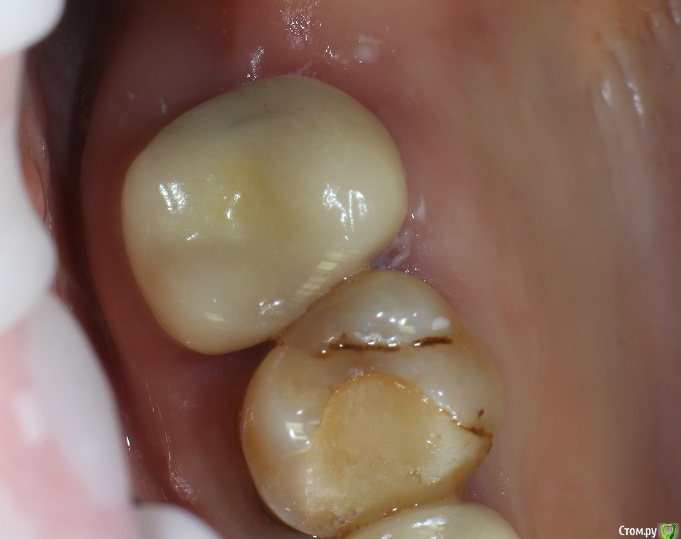

Кейс под названием: Что для тебя успешное эндо?

Пациент: девушка 16 лет. Задача дотянуть зуб сколько сможем по времени, затем имплантация.

Исходная ситуация:  симптоматический апикальный периодонтит. Отломок в медиально-щечном канале.IMG_20210716_134030.thumb.jpg.0b754f1cf44f10a3d2e05ed70884f5b7.jpg

Бился примерно 2 часа, Прошел медиально-язычный. Немного обошел обломок, за ним стопорюсь. Дистальный глухо. Оставил пульпосептин, готовился к удалению.

На следующем приеме жалоб нет, принял решение пломбировать что есть.

С пацом решили: если за 3 месяца не появится болей, и в прицельном не появится разряжение - то коронуем.

3 месяца спустя:

IMG_20210716_134129.thumb.jpg.71631666cf042a4c7352572d6c371b77.jpg

Устанавливаем коронку.

Прошло 1.5 года.

Звонит: ходуном ходит зуб. Думаю: ну, здравствуй, обострение, здравствуй, удаление. Пришла, оказывается расцементировка коронки. Делаем снимок:

IMG_20210716_134216.thumb.jpg.209b4330c838774d9bf6e170ae51304f.jpg